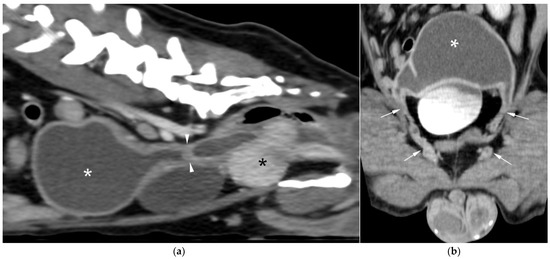

Uterus masculinus is a rare disorder of sexual development in males, characterized by the presence of tubular female genitalia. Diagnostic imaging reports of infected uterus masculinus are limited. We describe the ultrasonographic and computed tomographic findings in three dogs, all presenting with abdominal distension, pain, and systemic infection. Imaging consistently revealed a fluid-filled, bicornuate structure arising from the prostate. In two dogs, the horns extended through the inguinal rings to the scrotal testes; in the third, with a prior left orchiectomy, both horns were intra-abdominal, the right ending in a peritoneal mass. Surgery and histopathology confirmed infected uterus masculinus, with Escherichia coli isolated from urine in all dogs and from the structure in two. Two dogs had Leydig cell tumors, one with concurrent uterine neoplasia; the third had an ovarian or ovotesticular granulosa cell tumor. Although rare, infected uterus masculinus is potentially life-threatening and should be considered in male dogs with abdominal pain, distension, or systemic infection. This is the first case series describing combined ultrasonographic and tomographic features of infected uterus masculinus, including novel findings such as cervix-like mural narrowing and fluid–fluid levels. It is also the first imaging description of an ovarian or ovotesticular tumor in a dog with uterus masculinus. Full article

Figure 1